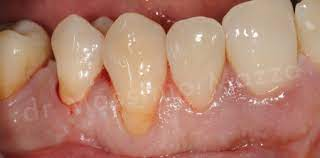

2. Abrasion

- Pathologic wear of teeth – abnormal habit, abnormal use of abrasives orally

- Eg. Pipe smoking, tobacco chewing, aggressive tooth brushing, abrasive dentifrices, pins & nails (carpenters)